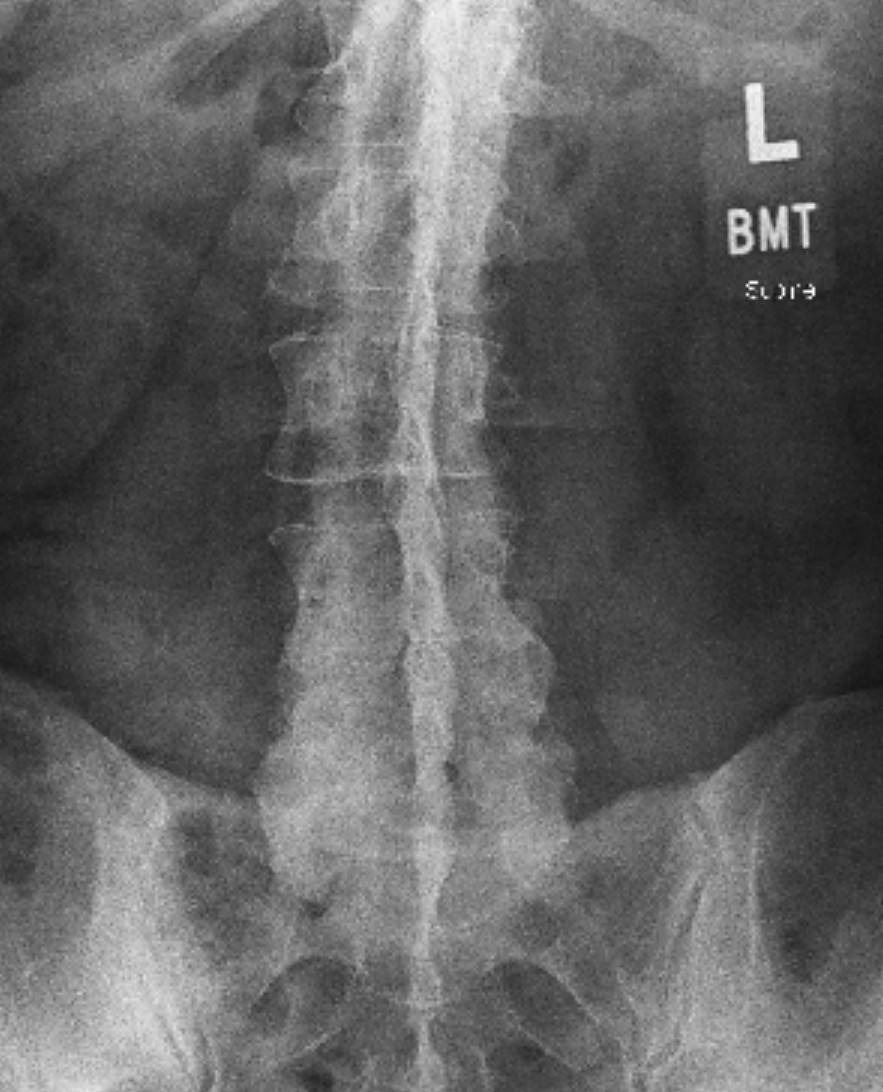

On top of the dental issue, I’m also dealing with Lumbar Spondylosis and Degenerative Disc Disease. My spine has a curvature to the right, with narrowing and arthropathy in the lower lumbar area. Recently, I also bruised my spine, which has made movement — and working — almost impossible.